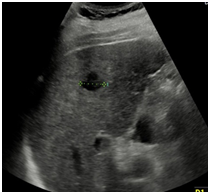

CT 또는 MRI로 병변 확인 초음파로 병변 확인